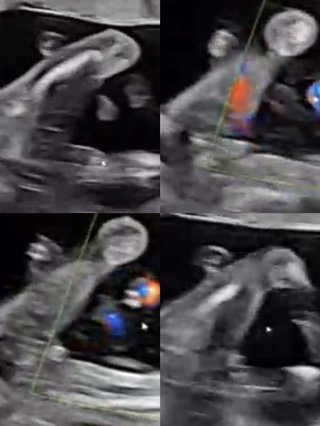

性別判断お願いします! 投稿画像

性別判断お願いします!